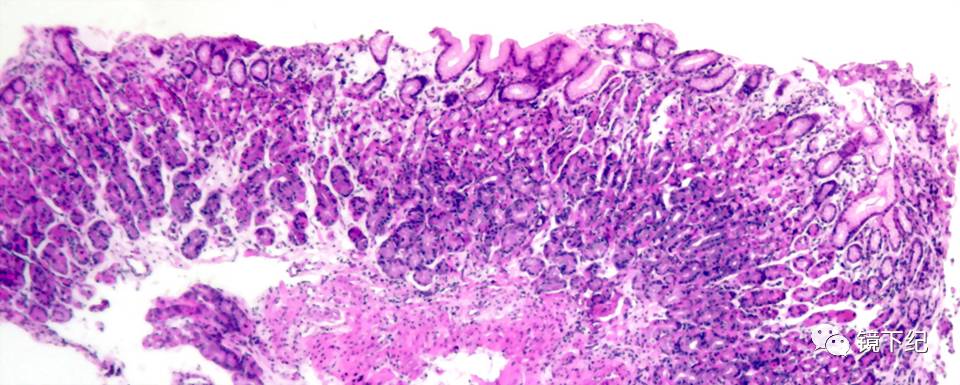

我想告诉大伙的是:“慢性胃炎”其实不是病,而是随着年龄的增加,胃部承担的工作量的累计,加上经年累月的饮食不当等,人们的胃器官不可避免地处于动态的“衰老”中,只要做胃镜检查并取一小粒胃粘膜到显微镜下观察(病理切片检查),几乎没有一个人是没有“慢性胃炎”的。这样的“生理性胃炎”是不需要治疗的。

图1 不需要治疗的慢性胃炎